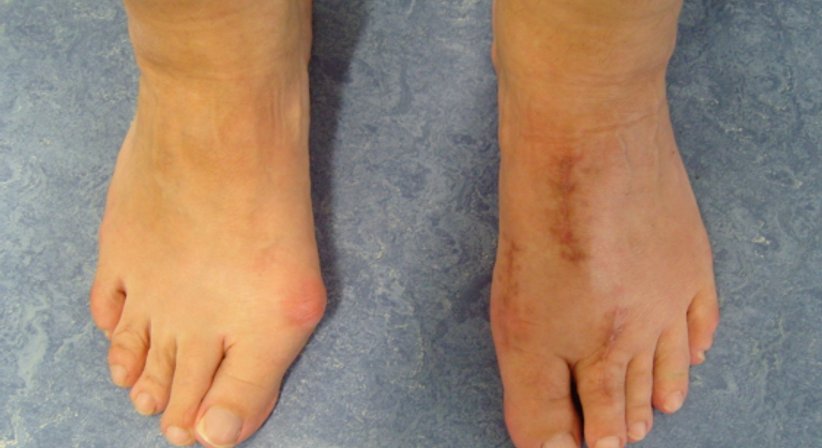

Der Hallux valgus ist eine fortschreitende Erkrankung des Vorfußes und die häufigste Fehlstellung der Zehen. Beim Hallux valgus ist die Großzehe nach außen in Richtung der kleineren Zehen abgeknickt, wodurch diese von ihrer Position verdrängt werden.

Der hervorstehende und für die Fehlstellung charakteristische Ballen drückt häufig gegen den Schuh, was mit der Zeit zu Schmerzen führt und die Gelenkkapsel anschwellen lässt. Nimmt die Schwellung zu, verstärkt sich wiederum die Reibung des Ballens am Schuh. Mit fortschreitendem Verlauf verändert sich auch die Gewichtsverlagerung des Fußes, nämlich weg von der Großzehe und hin zu den kleineren Zehen, was zu deren Überlastung und in weiterer Folge zu Schmerzen im Bereich vom Mittelfuß führen kann. Weitere mögliche Spätfolgen sind ein verändertes Gangbild, Gangunsicherheit, weitere Fehlstellungen (z.B. Krallen- und Hammerzehen), Arthrose am Großzehengrundgelenk und andere.